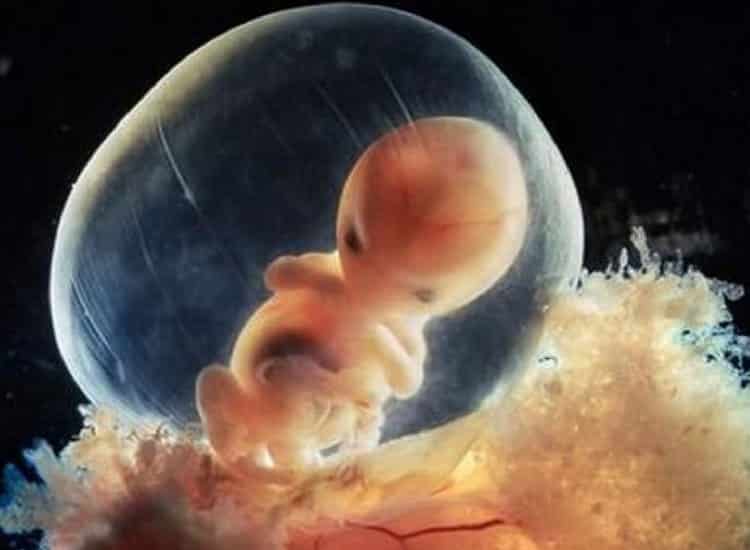

Dentro da placenta, este é o feto após 8 semanas de gestação

Com 10 semanas já é possível notar a formação das pálpebras